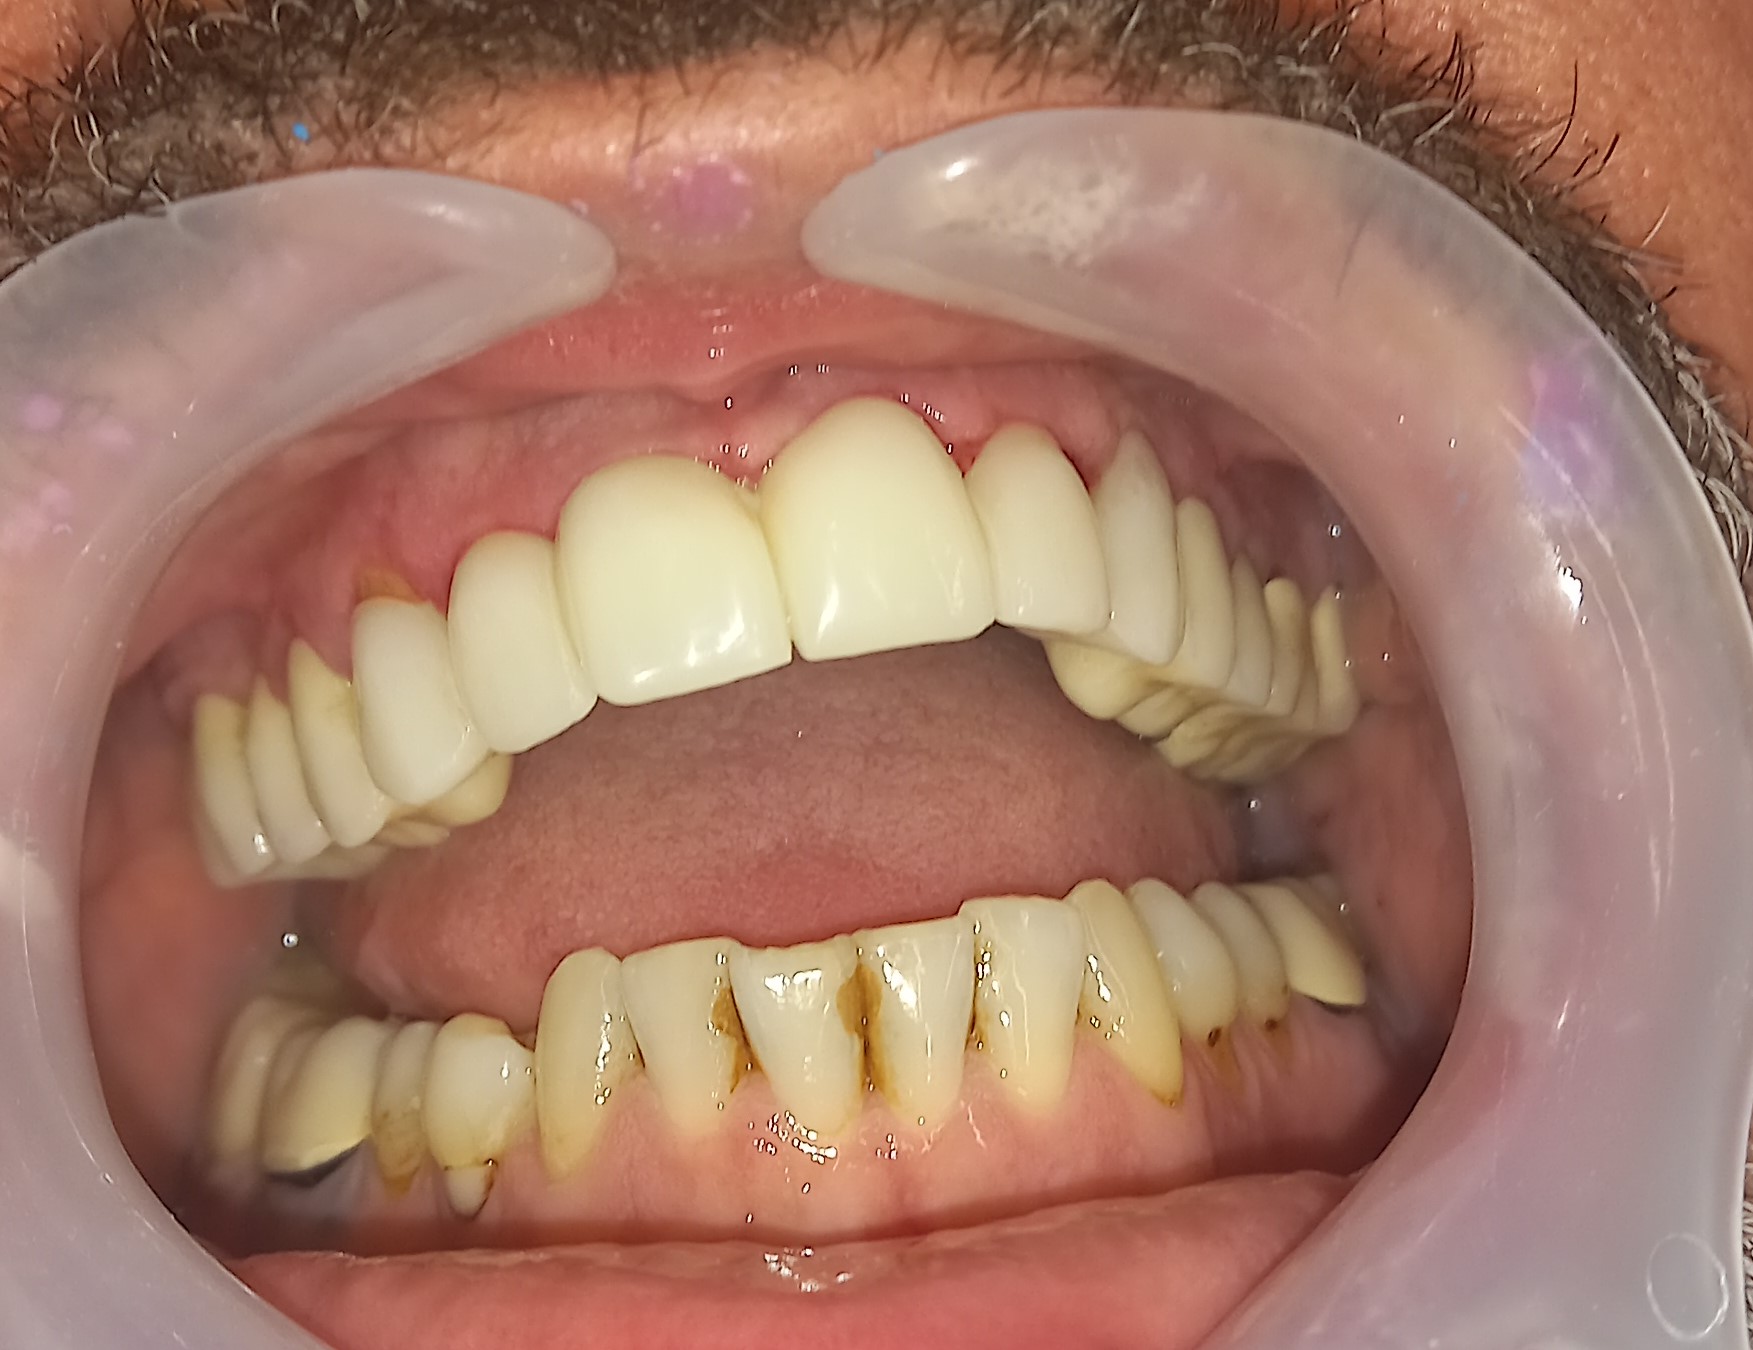

Ο ασθενής δεν είναι ευχαριστημένος με την αισθητική των 6 άνω πρόσθιων δοντιών. Επιπρόσθετα αυτά τα δόντια είχαν παλιές μεγάλες ανασυστάσεις, οι οποίες είχαν επανατερηδονιστεί. Για όλους τους ανωτέρους λόγους αποφασίστηκε, μετά από την απαραίτητη συζήτηση με τον ασθενή η αποκατάσταση των δοντιών με ολοκεραμικές θήκες. Τα δόντια τροχίστηκαν, αντικαταστάθηκαν οι παλιές εμφράξεις των δοντιών και στη συνέχεια λήφθηκαν αποτυπώματα, τα οποία στάλθηκαν στον οδοντοτεχνίτη. Σε όλη τη διάρκεια, που ο οδοντοτεχνίτης κατασκεύαζε τις νέες προσθετικές αποκαταστάσεις ο ασθενής φορούσε προσωρινές θήκες, οι οποίες είχαν ικανοποιητική αισθητική εμφάνιση.

Είναι σημαντικό να τονιστεί οτι ο ασθενής επιθυμούσε οι θήκες των 6 άνω πρόσθιων δοντιών να είναι αισθητά λευκές, παρόλο που διέφεραν χρωματικά από τα υπόλοιπα δόντια.

Ο ασθενής είναι ευχαριστημένος τόσο με την αισθητική όσο και με τη λειτουργία των νέων προσθετικών αποκαταστάσεων.

Αρχική κλινική εικόνα των 6 άνω πρόσθιων δοντιών

Προσωρινή αποκατάσταση των 6 άνω πρόσθιων δοντιών

Τελική κλινική εικόνα των 6 άνω πρόσθιων δοντιών